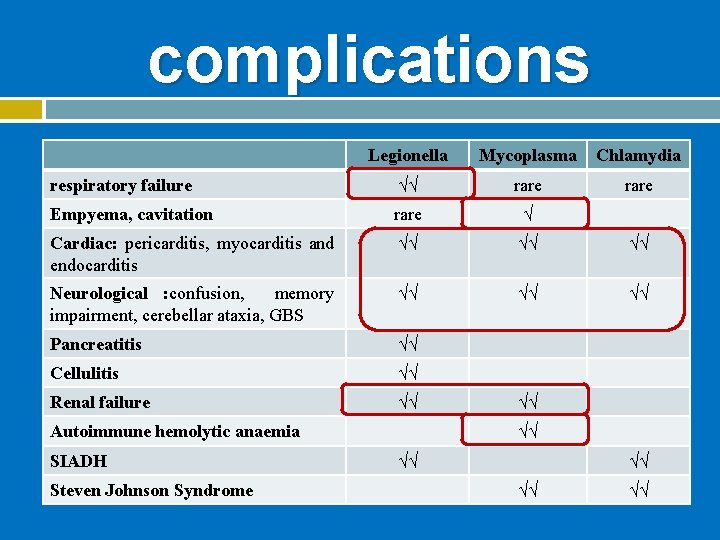

complications Legionella Mycoplasma Chlamydia respiratory failure √√ rare Empyema, cavitation rare √ Cardiac: pericarditis, myocarditis and endocarditis √√ √√ √√ Neurological : confusion, memory impairment, cerebellar ataxia, GBS √√ √√ √√ Pancreatitis √√ Cellulitis √√ Renal failure √√ Autoimmune hemolytic anaemia SIADH Steven Johnson Syndrome √√ √√ √√